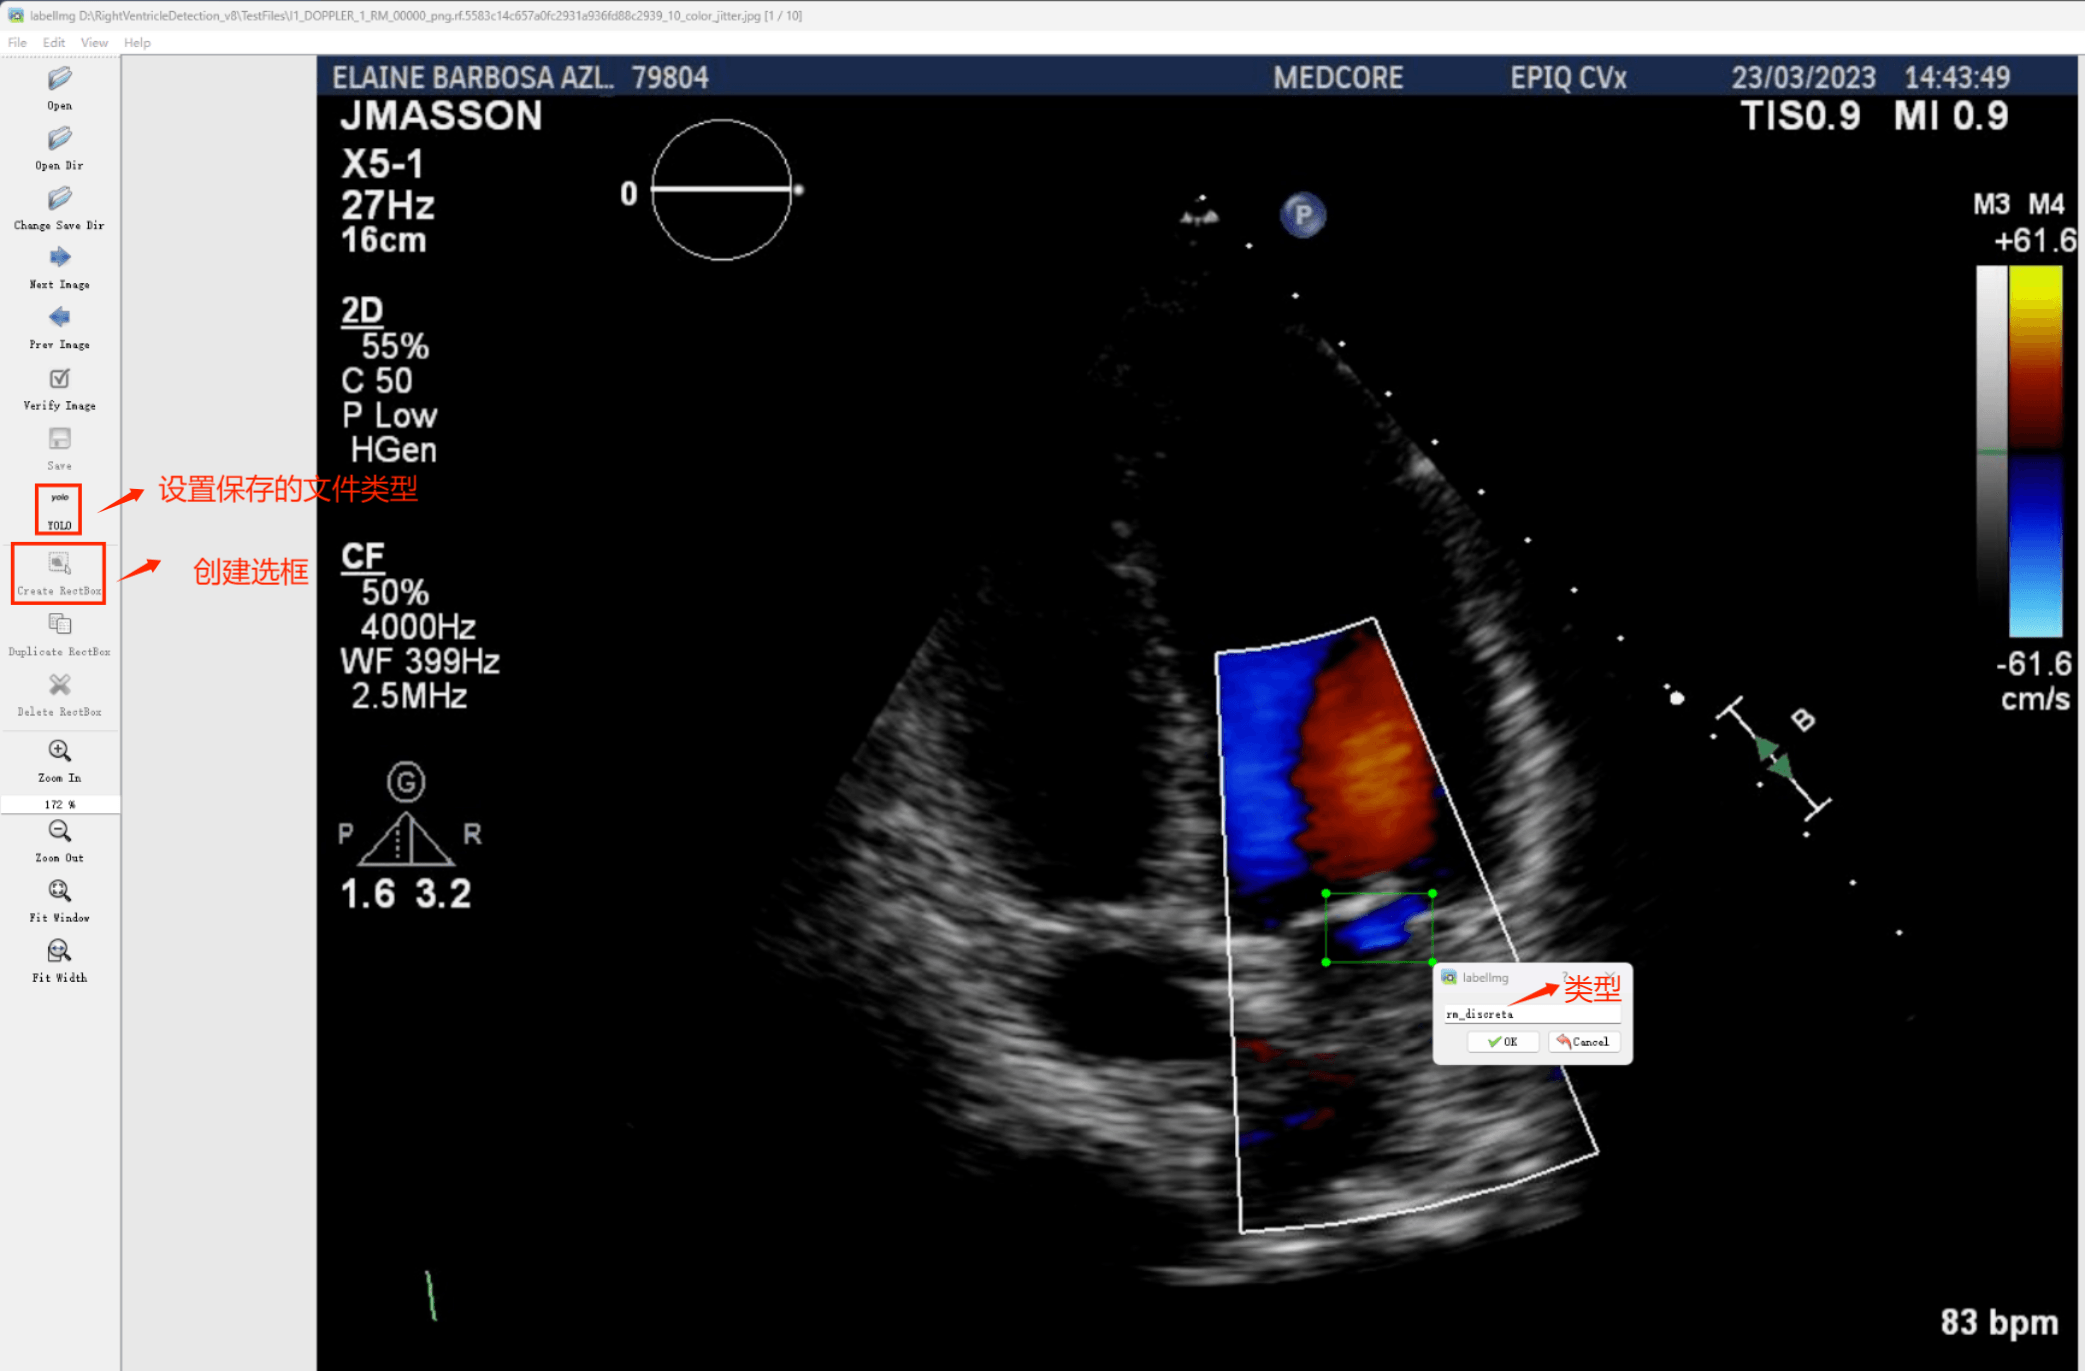

(1)labelimg:开源的图像标注工具,标签可用于分类和目标检测,它是用python写的,并使用Qt作为其图形界面,简单好用(虽然是英文版的)。其注释以 PASCAL VOC格式保存为XML文件,这是ImageNet使用的格式。此外,它还支持 COCO数据集格式。

初识labelimg

打开后,我们自己设置一下

在View中勾选Auto Save mode

接下来我们打开需要标注的图片文件夹

并设置标注文件保存的目录(上图中的Change Save Dir)

接下来就开始标注,画框,标记目标的label,然后d切换到下一张继续标注,不断重复重复。

(4)YOLO模式创建标签的样式

存放标签信息的文件的文件名为与图片名相同,内容由N行5列数据组成。

每一行代表标注的一个目标,通常包括五个数据,从左到右依次为:类别id、x_center、y_center、width、height。

其中:

–x类别id代表标注目标的类别;

–x_center和y_center代表标注框的相对中心坐标;

–xwidth和height代表标注框的相对宽和高。

注意:这里的中心点坐标、宽和高都是相对数据!!!

存放标签类别的文件的文件名为classes.txt (固定不变),用于存放创建的标签类别。